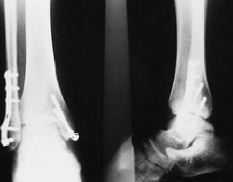

Caso clínico número 1 (Figs. 1A, 1B y 2)

Fig. 1, A y B.--Radiografía simple, anteroposterior y lateral, de ambos tobillos previa a la intervención. En el tobillo derecho se aprecian signos artrósicos avanzados. Caso clínico núm. 1.

Fig. 1, A and B.--Plain radiographs, anteroposterior and lateral, of both ankles before surgery. The right ankle shows signs of advanced arthrosis. Clinical case 1.

Fig. 2.--Radiografía simple, anteroposterior y lateral, del tobillo derecho tras la implantación de la prótesis. Se observa colapso astragalino, reabsorción ósea periprotésica y gran deformidad articular. Caso clínico núm. 1.

Fig. 2.--Plain radiographs, anteroposterior and lateral, of the right ankle after arthroplasty. Collapse of the astragalus, periprosthetic bone resorption, and major articular deformity. Clinical case 2.

Se trata de un paciente de cincuenta y ocho años con antecedentes de fibrilación auricular, insuficiencia venosa periférica, paludismo, pancreatitis, obesidad y prótesis total de rodilla izquierda.

Acude a nuestra consulta por presentar dolor y limitación funcional de varios años de evolución, sobre todo, en tobillo derecho.

La radiografía simple muestra importantes cambios degenerativos en la articulación tibio-peroneo-astragalina (pinzamiento de la interlínea articular, osteofitos, etc.).

Se propone la implantación de una prótesis de tobillo, que se lleva a cabo bajo profilaxis antibiótica y antitrombótica. En el curso de la intervención se produce una fractura yatrógena en maleolo interno, que se fija con un tornillo.

Durante el postoperatorio, presenta una zona de necrosis a nivel de la herida quirúrgica con exposición tendinosa que requirió la realización de un injerto cutáneo laminar por parte del Servicio de Cirugía Plástica.

En la actualidad, presenta molestias importantes en tobillo derecho, observándose en la radiografía simple colapso astragalino, reabsorción ósea periprotésica y gran deformidad articular. Se propone para artrodesis de tobillo por movilización de la prótesis.